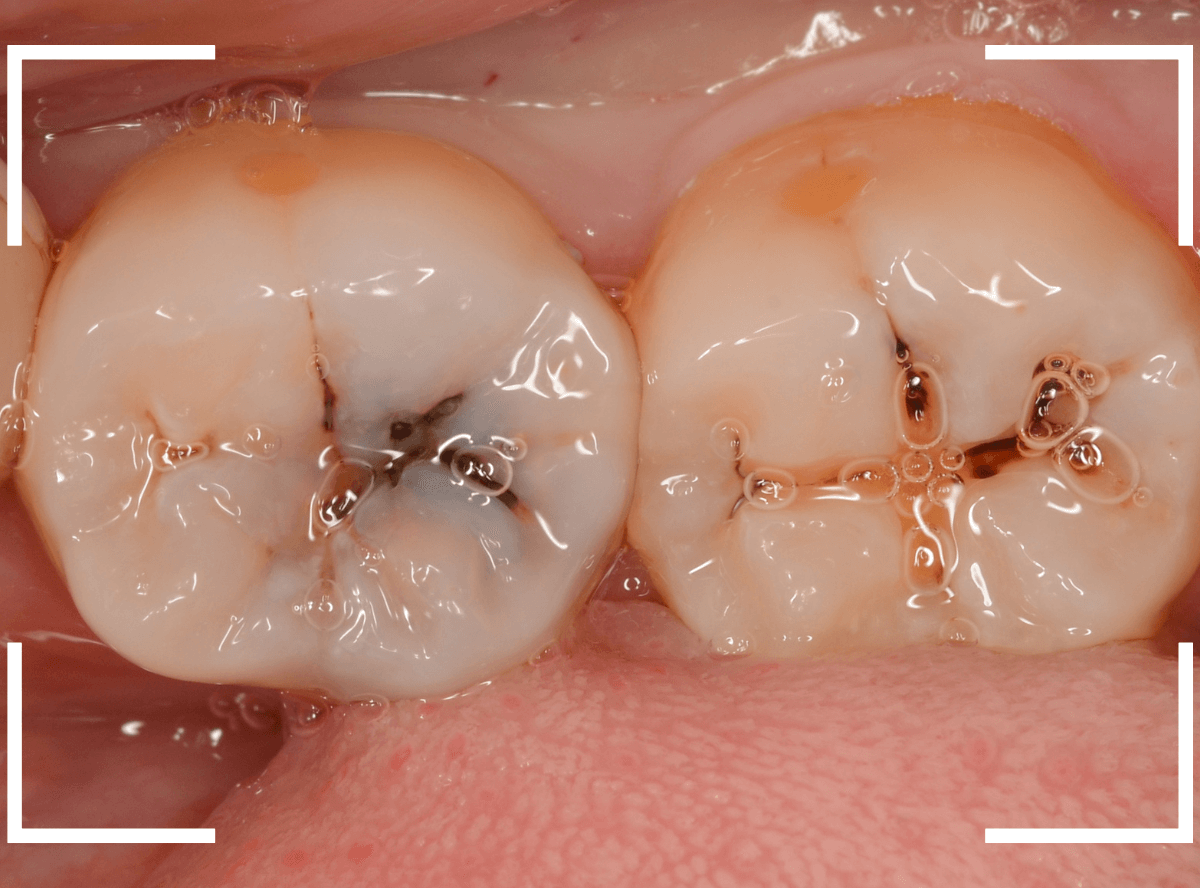

裂溝部分を少し削ると、中は虫歯で大きな空洞になっていました。

ある程度、虫歯を除去したところで、う蝕検知液で確認します。

真っ赤に染まり、まだ虫歯が取り切れていないのがわかります。

神経まで近づいてきたので、慎重に虫歯を除去します。

全ての虫歯を除去したところです。

神経スレスレのところまで虫歯が広がっていました。

歯を上から確認すると、溝の周りが虫歯がありそうです。

レントゲン写真で確認すると、やはり、中で虫歯が進行していました。

このように、入り口が狭くても、中で広がっている虫歯はとても多いです。

虫歯の部分を少しずつ削りながら、虫歯を確認します。

左側の歯はかなり虫歯が広がっているのがわかりますね。

典型的な、内部で広がる小窩裂溝う蝕です。